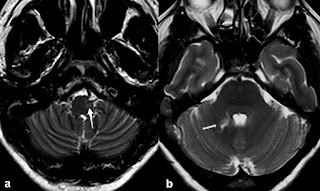

Figura 2. Degeneración olivar hipertrófica unilateral (izquierda). a) Imagen axial potenciada en T2 que muestra la oliva bulbar izquierda hiperintensa (flecha blanca). b) Imagen axial potenciada en T2 que muestra la afectación del pedúnculo cerebeloso superior derecho (flecha blanca) por un infarto isquémico en el territorio de la arteria cerebelosa superior.

Figura 4. Degeneración olivar hipertrófica unilateral. a) Imagen axial potenciada en T2 que muestra la oliva bulbar derecha hiperintensa y aumentada de tamaño (flecha blanca). b) Imagen axial potenciada en T1 con contraste intravenoso que muestra un ependimoma del cuarto ventrículo antes de la exéresis quirúrgica (flecha blanca).

Figura 5. Degeneración olivar hipertrófica bilateral secundaria a un hematoma protuberancial probablemente por lesión del tracto tegmental central bilateral y posiblemente del tracto dentorrubral bilateral. a) Imagen axial potenciada en T2 que muestra las dos olivas bulbares hiperintensas y aumentadas de tamaño (doble flecha blanca). b) Imagen axial potenciada en T2 que muestra una lesión hipeintensa con un halo hipointenso (hemosiderina) correspondiente al hematoma protuberancial (flecha blanca).

Figura 6. Degeneración olivar hipertrófica unilateral (derecha) secundaria a un hematoma cerebeloso izquierdo por lesión del núcleo dentado izquierdo y tracto dentorrubral. a) Imagen axial potenciada en T2 que muestra la oliva bulbar derecha hiperintensa y aumentada de volumen (flecha blanca) y un hematoma en el hemisferio cerebeloso izquierdo (flecha negra). b) Imagen FLAIR T2 que muestra la oliva bulbar derecha hiperintensa y aumentada de volumen (flecha blanca).